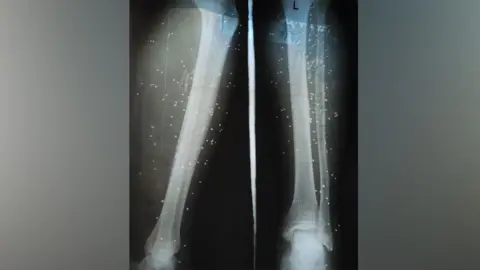

A poignant case highlighted by Devendra, a farmer who lost his leg after being bitten by a snake, underscores the dire consequences of delayed treatment. He sought hospital assistance four days post-bite, ultimately resulting in amputation. Such tragedies are not isolated; estimates have shown that up to 1.2 million snakebite deaths occurred in India between 2000 and 2019.